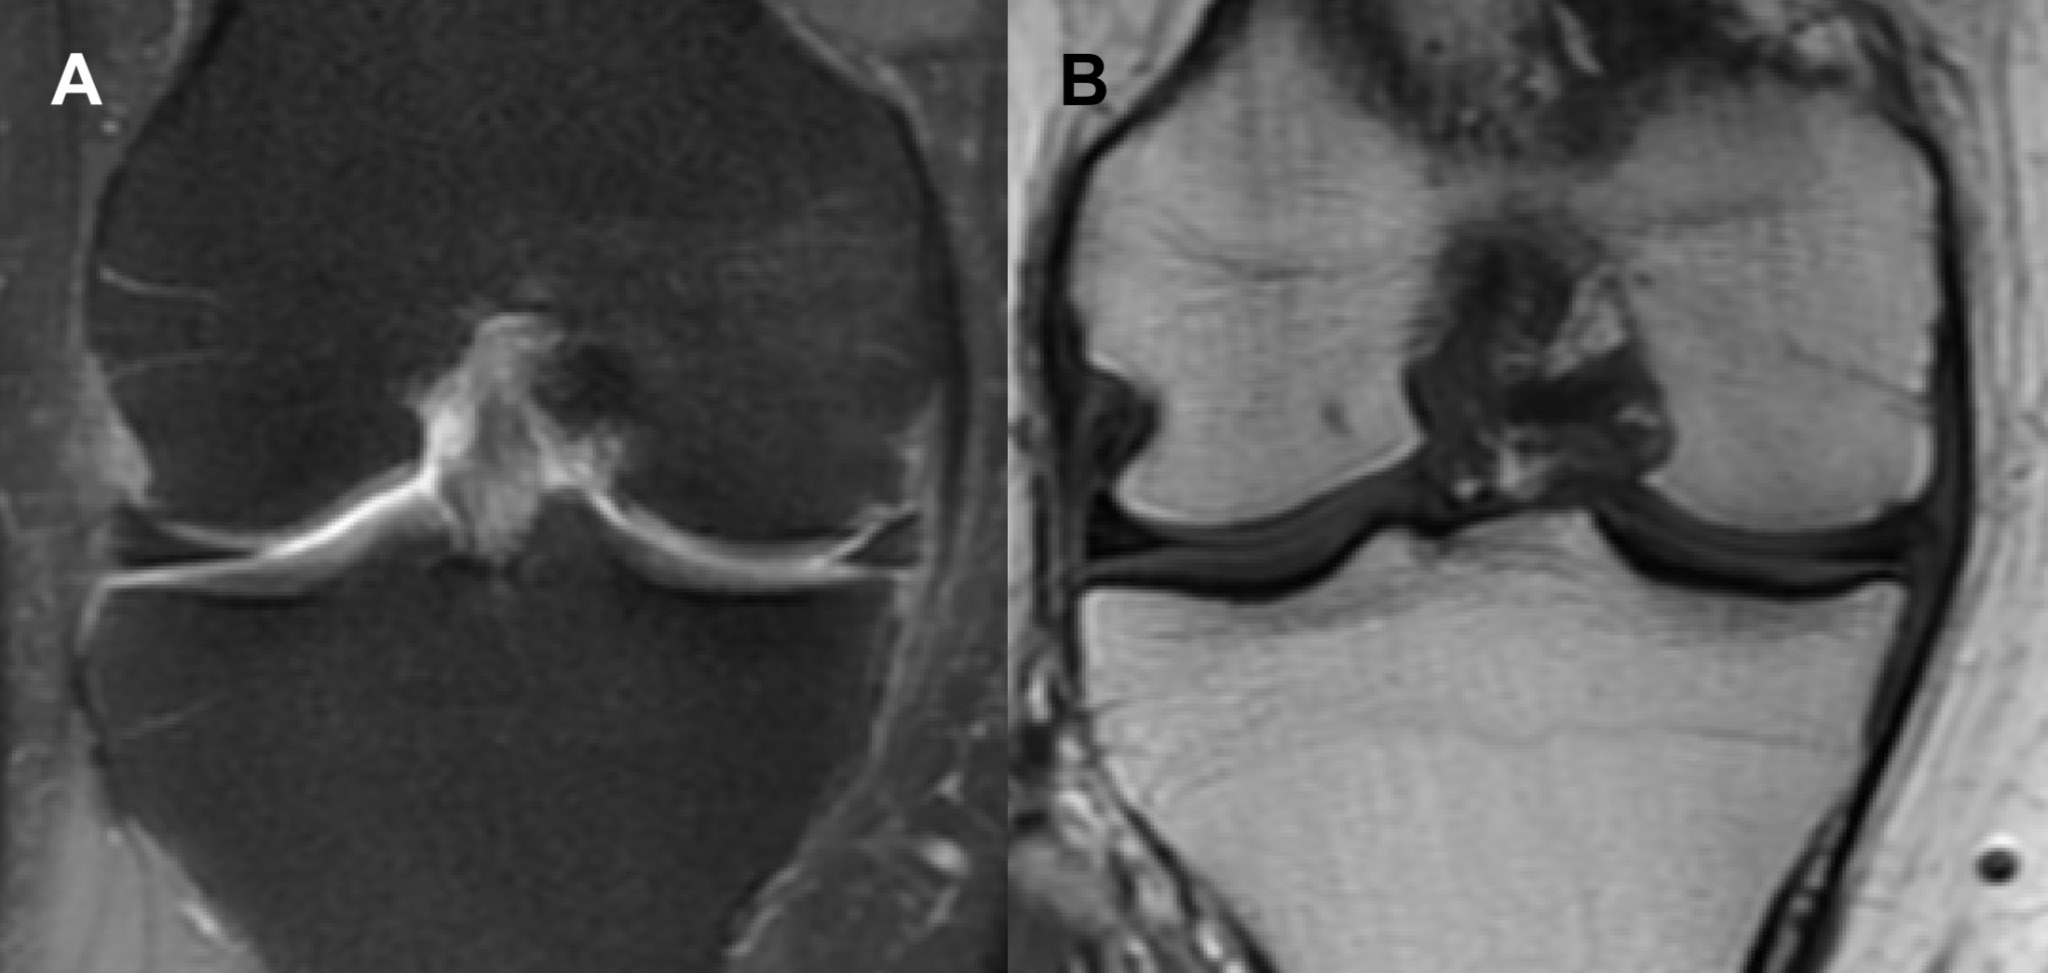

The 2 cases of PCT-SONK presented in this study add to the differential diagnosis of sudden knee pain in uninjured patients during the ongoing pandemic. It is particularly noteworthy that the radiological findings that constitute PCT-SONK, although similar in both cases presented in this study, are radiologically distinct in appearance from classic SONK (Figure 6). No subchondral bone thickening was observed, and the bone edema was more diffuse in the whole femoral condyle, in contrast to focal edema, which is concentrated mainly around the subchondral region and typically observed in classic SONK (Table 1).

Fig. 1. Magnetic resonance imaging (MRI) coronal view of the right knee (Case 1) performed in the symptomatic period. There is diffuse increase in signal in the medial femoral condyle in both (A) short tau inversion recovery (STIR) fast spin echo (FSE) and (B) proton density (PD) sequences. It is noteworthy that the signal intensity in the subchondral bone is only slightly affected in the (B) PD sequence. Edema of the soft tissues on the medial side of the joint is also clearly visible

Fig. 2. Follow-up magnetic resonance imaging (MRI) coronal view of the right knee (Case 1) performed after the resolution of symptoms. The signal in the medial femoral condyle in both (A) short tau inversion recovery (STIR) fast spin echo (FSE) and (B) proton density (PD) sequences is almost normal. It is noteworthy that there is no visible soft tissue edema.

Fig. 6. Radiological (coronal magnetic resonance imaging (MRI) views) appearance of classic spontaneous osteonecrosis of the knee (SONK) in the right knee. There is a focal signal increase in subchondral bone in both (A) short tau inversion recovery (STIR) fast spin echo (FSE) and (B) proton density (PD) magnetic resonance imaging (MRI) sequences